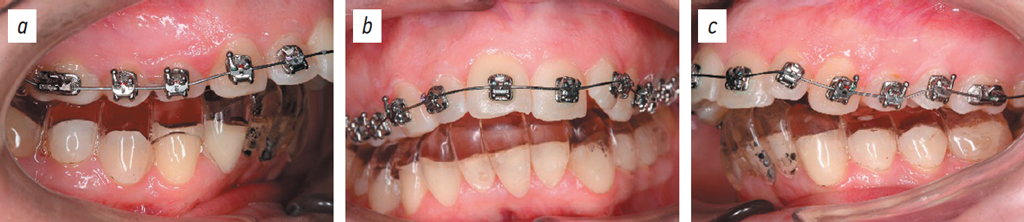

After installing braces on the mandible, nano-osteoperforation in FDI quadrants 3 and 4 was performed. Figs. 13 and 14 show the effect of nano-osteoperforation after 4 weeks of orthodontic treatment.

Orthodontic microimplants were then placed in FDI quadrants 1 and 2 for occlusal plane correction (Figs. 15, 16).

Fig. 15. Dental arches, right lateral projection (a), posteroanterior projection (b), left lateral projection (c).

Рис. 15. Зубные ряды: боковая правая проекция (a), прямая проекция (b), боковая левая проекция (c).

The outcomes of orthodontic treatment are presented in Figs. 19–21.

Fig. 19. Dental arches: lateral right projection (a), posteroanterior projection (b), lateral left projection (c).

Рис. 19. Зубные ряды: боковая правая проекция (a), передняя проекция (b), боковая левая проекция (c).

This clinical case demonstrated a 2-fold reduction in treatment duration compared to conventional approaches.